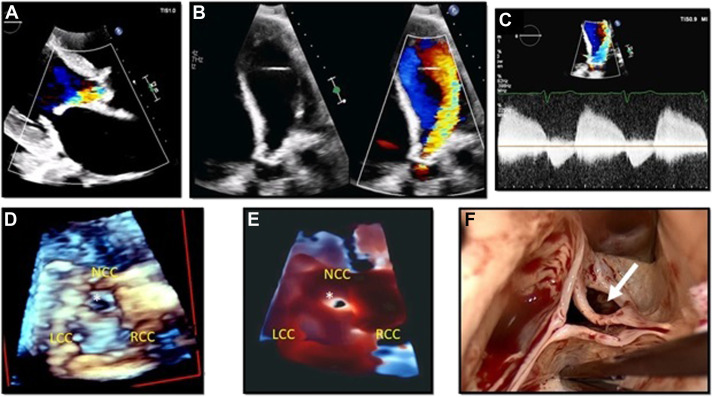

#JADEL Just dropped @CASEfromASE 42 man with multiple intracardiac masses Dx & Rx guided by MMI from @robertomlang: https://t.co/hEuRMolimh Why Read This? - Echo, CT & Path correlation - Masses in 3 chambers is rare - MMI guides decision making @ASE360 #EchoFlorida22